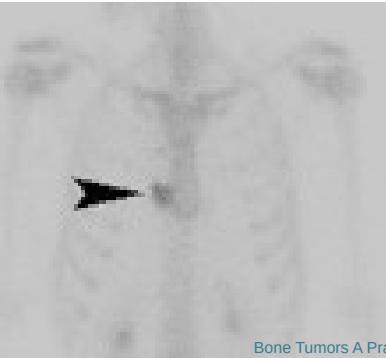

Additional Imaging

- Bone scan:

- Primary lesion

- Metastasis